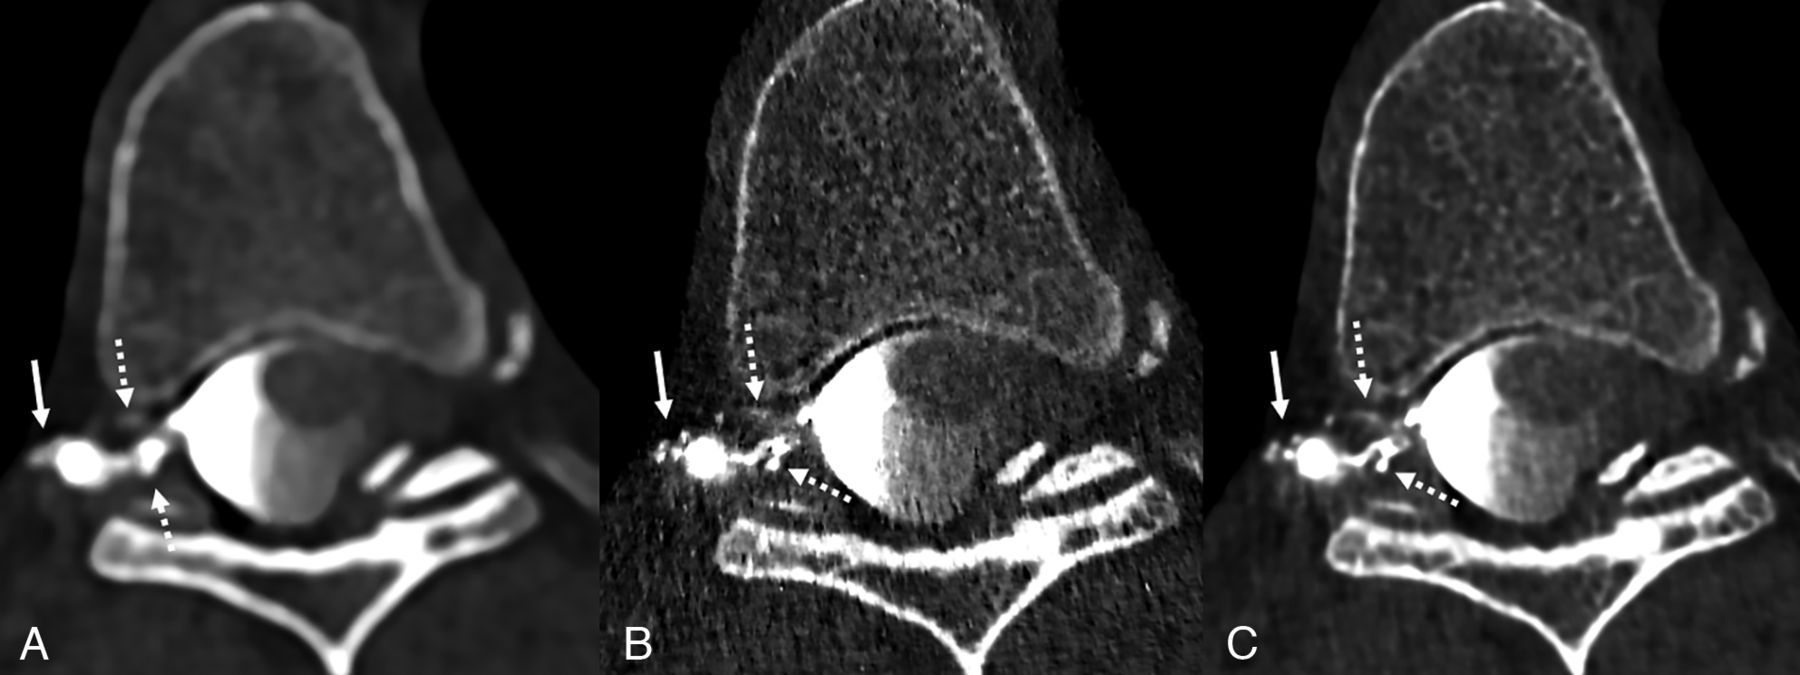

The imaging protocol and technique for PC-CTM have been previously detailed.6 Briefly, patients are placed in the decubitus Trendelenburg position on the PCCT table (NAEOTOM Alpha; Siemens), and 3–6 scans of the spine are obtained during active injection of 5 mL of Omnipaque 300 (GE Healthcare) after a lumbar puncture with a 22- or 20-ga spinal needle. Two of these scans are obtained in an ultra-high-resolution mode, permitting 0.2-mm section thickness recontructions. The needle is removed, and the process is repeated with the patient in the contralateral decubitus position after placing a new spinal needle. Initially, we reconstructed images using a low-energy threshold (T3D) and a Br56 kernel at a quantum iterative reconstruction (QIR) strength of 4 (Figs 1A, 2A, and 3A). When a sharper Qr89 kernel was used, the resulting images were too noisy, impairing diagnostic performance (Figs 1B, 2B, and 3B).

Axial low-energy thresholded (T3D) images in a 50-year-old woman with a right T6 CVF. Images were reconstructed using a Br56 kernel (A), a sharper Qr89 kernel (B), and a Qr89 kernel after denoising with the trained model (C), all presented at the same section and window/level settings. The Br56 kernel demonstrates amorphous opacification around a right T6 diverticulum (A, solid arrow) and possible venous opacification in the internal vertebral venous plexus (A, dashed arrows). The Qr89 kernel more clearly delineates individual external vertebral veins (B, solid arrow), though the image is overall degraded secondary to noise (B, dashed arrows). The denoised Qr89 image clearly identifies all the involved veins, including the external vertebral veins (C, solid arrow) and ventral/dorsal internal vertebral venous plexus (C, dashed arrows).